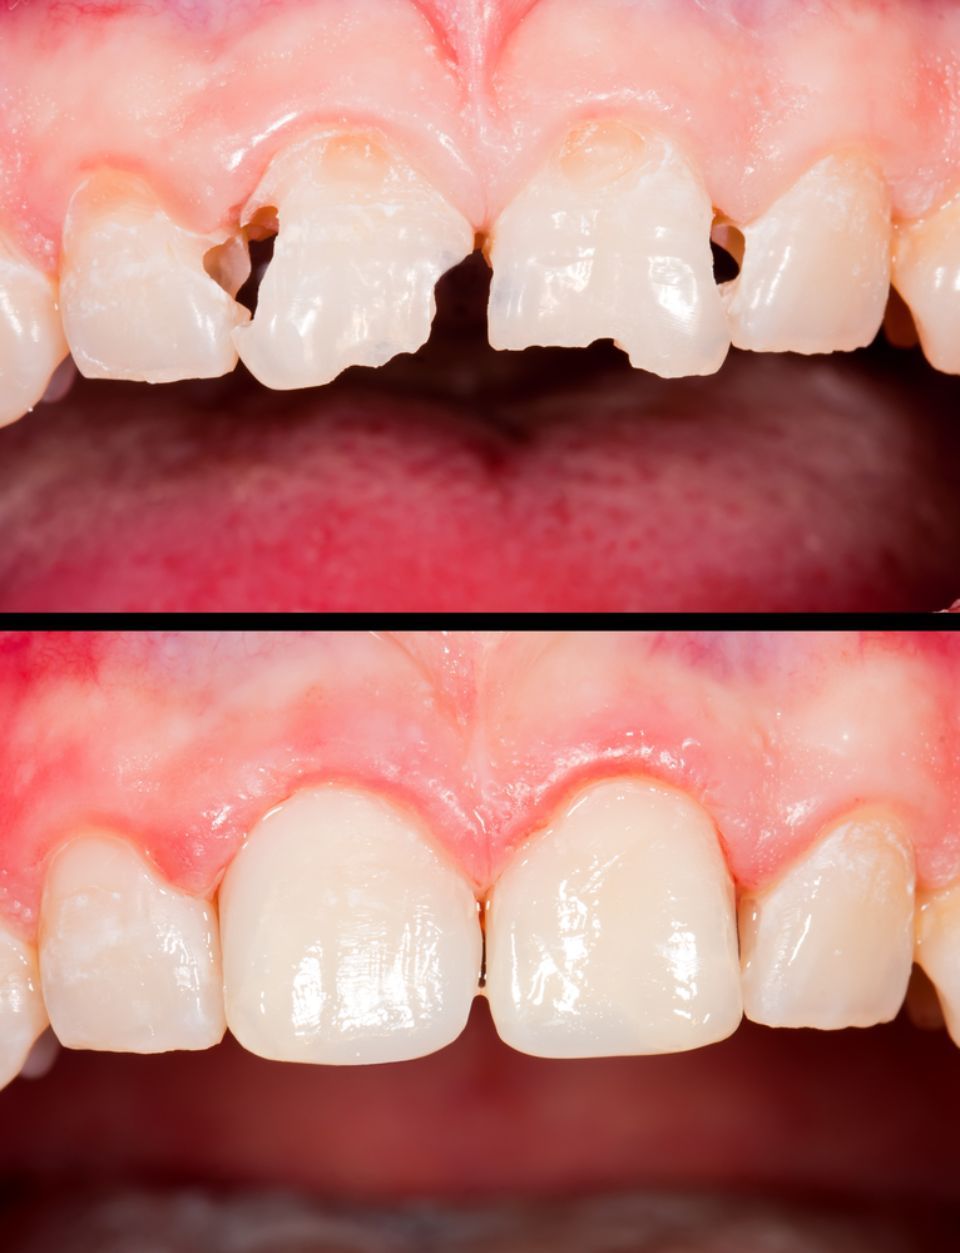

Estética dental

La apariencia de los dientes se puede mejorar. El equipo especialista evaluará cada caso para adoptar la técnica más adecuada: blanqueamiento dental, restauraciones con composite, carillas de cerámica, coronas de metal-cerámica, coronas de circonio, ortodoncia, cirugía estética periodontal ....